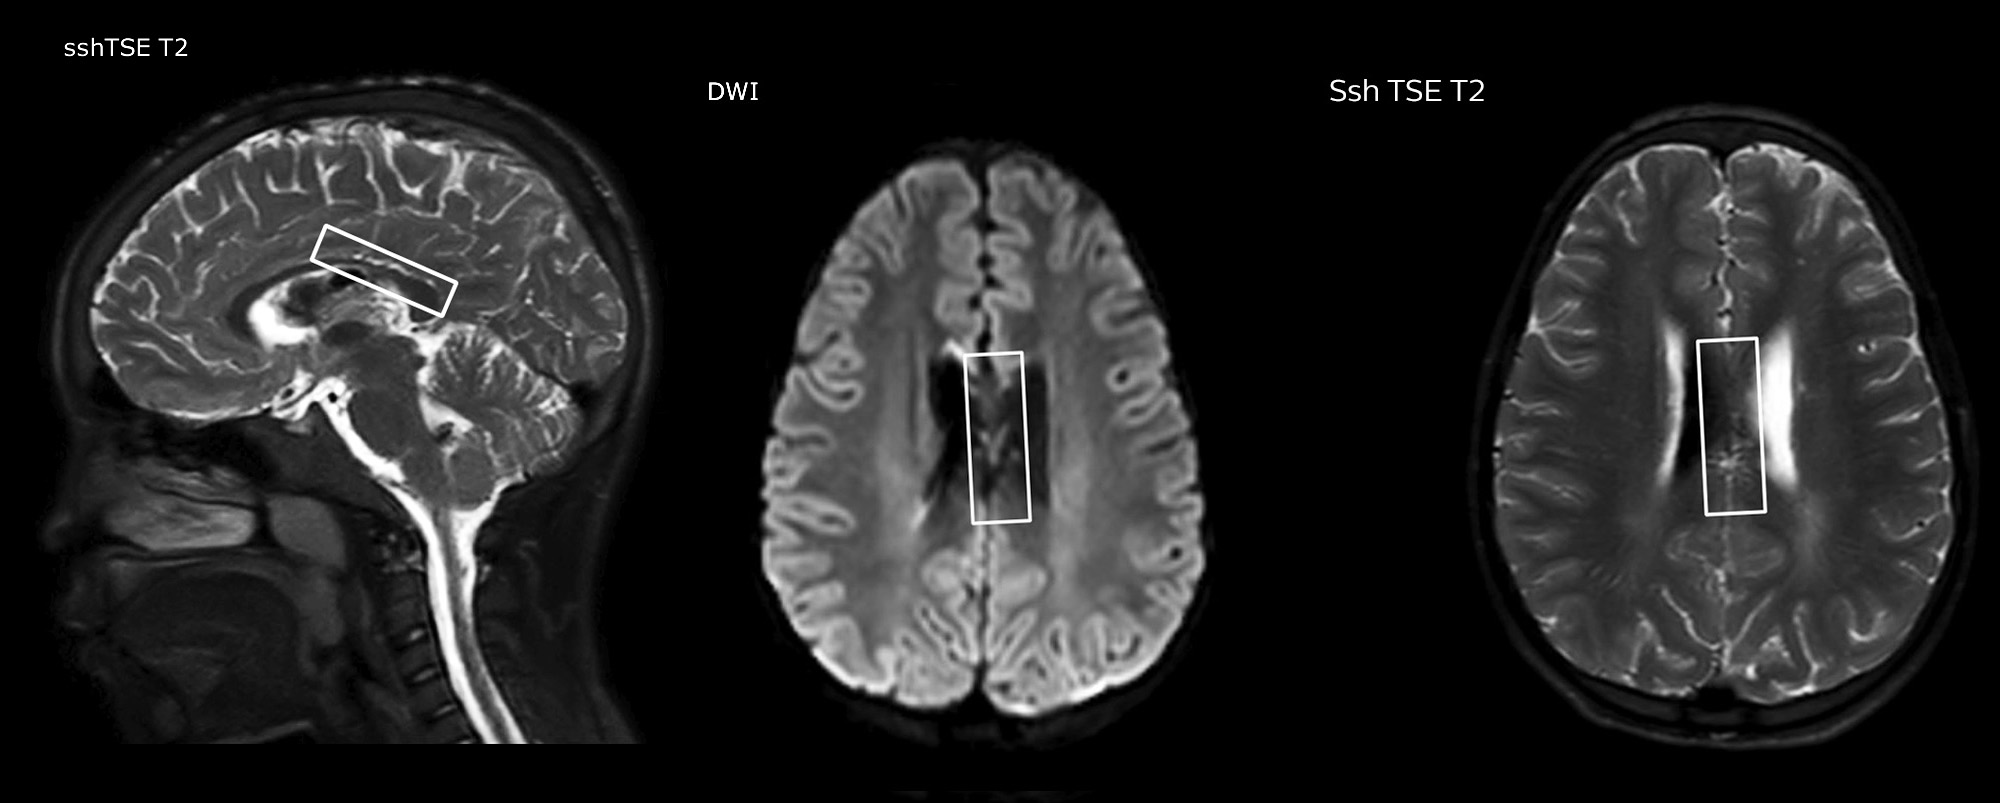

Routinely obtaining homogeneous fat suppression under virtually all conditions with mDIXON TSE

Philips mDIXON TSE is a two-point DIXON technique that separates water and fat signals, for time-efficient fat-free imaging, even in challenging neuro anatomy.

“mDIXON TSE has been one of the most significant improvements in imaging sequences that we have utilized to date at PCH,” says Dr. Miller. “Its multi-parametric acquisition allows us to obtain fat suppressed images and equivalent non-fat suppressed T2 images all in the same sequence. In addition, prior methods of fat suppression could be artifactually corrupted by poor patient anatomy or poor operator application, but with mDIXON we now have a robust and reliable method of fat suppression.”

Fat saturation is historically challenging at the ends of fields of view, especially in total spine imaging and in difficult patient anatomy such as the lower regions of the neck. “Due to the unique fat suppression capabilities of mDIXON, however, these challenges no long apply,” says Dr. Miller. “We routinely obtain homogeneous fat suppression under virtually all conditions. It has also led to some efficiencies by not having to repeat sequences because of that technical failure.”

mDIXON TSE makes a difference

“mDIXON TSE is most useful in patients with lesions or abnormalities in the soft tissues such as the face and neck, and for patients with contrast enhancing abnormalities that are mostly visible with fat suppression,” says Dr. Miller. “All our spine imaging now routinely contains mDIXON water-only T2 images, and this allows us to identify pathology that may be obscured by non-fat suppressed imaging such as injuries of the bone. And it’s not necessary to obtain additional standard TSE T2 images because the in-phase mDIXON images are equivalent to standard TSE T2 images.”

“mDIXON TSE has increased our diagnostic confidence in ruling in or ruling out abnormalities in which fat suppression is critical to diagnosis, such as metastatic disease or osseous abnormalities.”